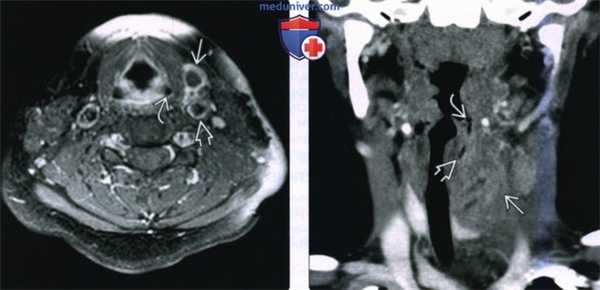

(Слева) При аксиальной МРТ Т1ВИ С+ FS визуализируется небольшая многокамерная киста, накапливающая контраст по типу «ободка», расположенная спереди от сонной артерии, находящейся в открытом состоянии, и снаружи от вершины левого грушевидного синуса.

(Справа) При корональной КТ с КУ визуализируется объемное образование воспалительного характера, смещающее левую долю щитовидной железы книзу. Ткани, окружающие свищевой ход, начинающийся на уровне вершины грушевидного синуса, воспалены.